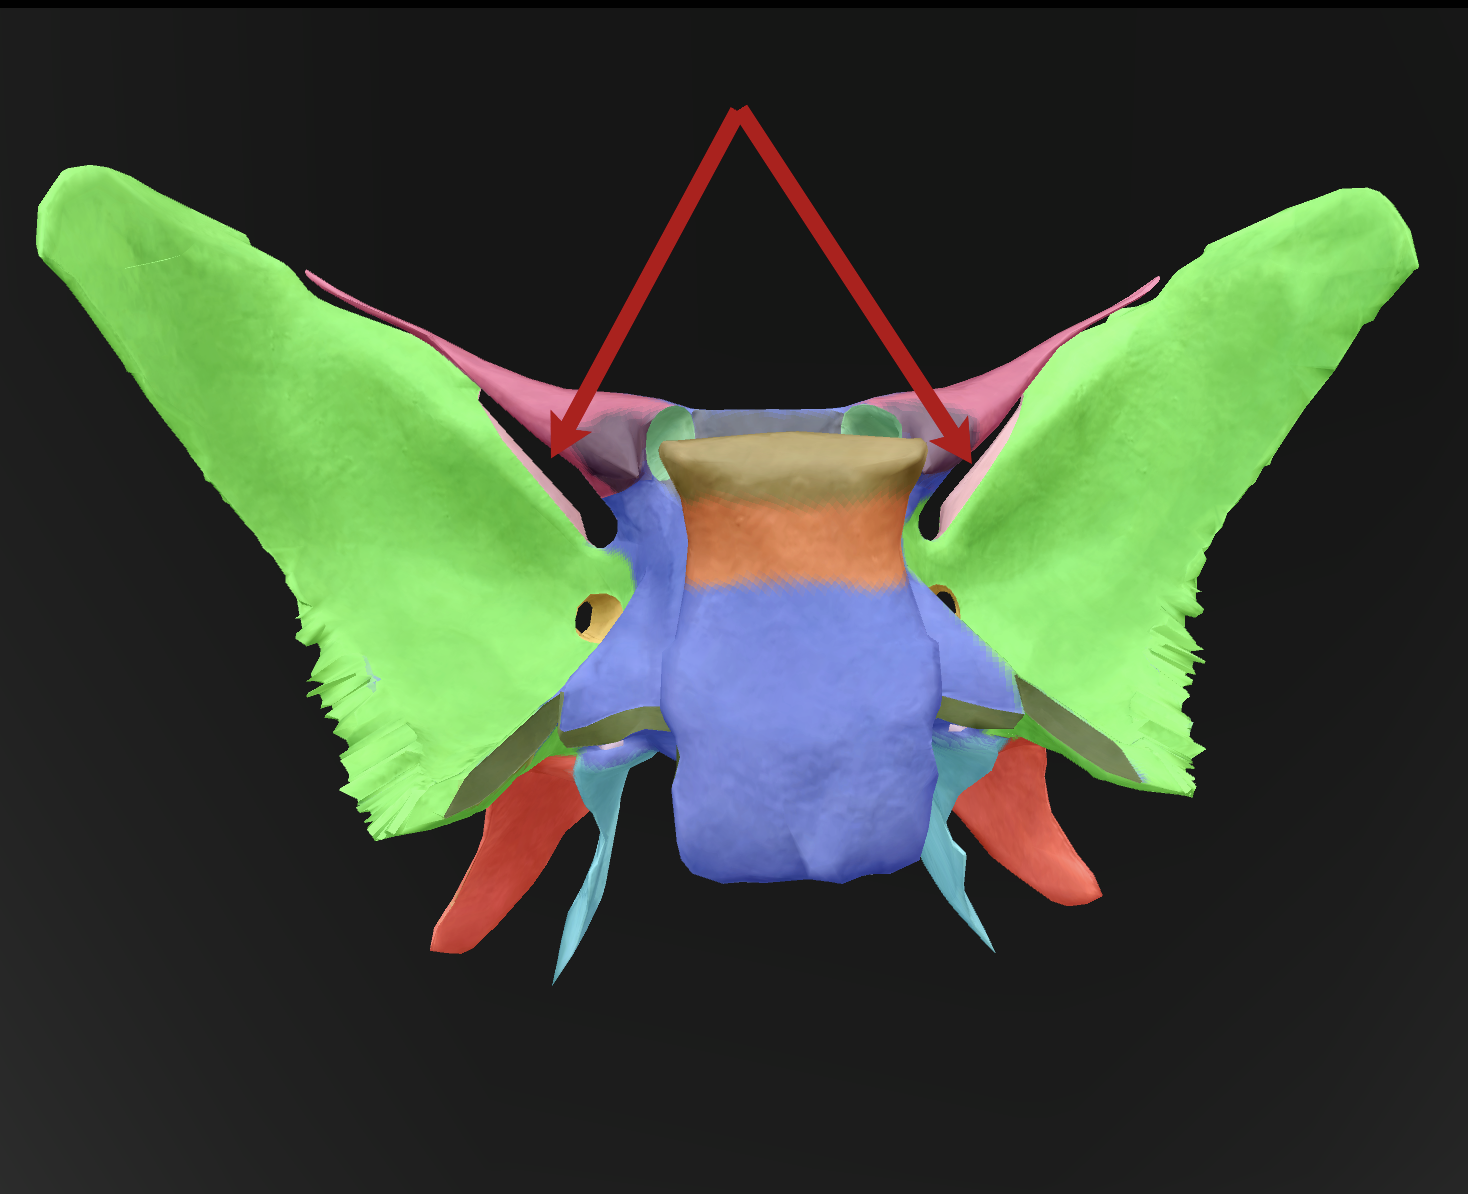

What is the name of this bone?

sphenoid bone

body

What is the name of this feature?

lesser wings

What is the name of this feature?

sella turcica

What is the name of this feature?

greater wings

What is the name of this feature? (the hole)

optic foramen

What is the name of this feature?

lateral pterygoid plate

What is the name of this feature?

medial pterygoid plate

What is the name of this feature?

superior orbital fissure